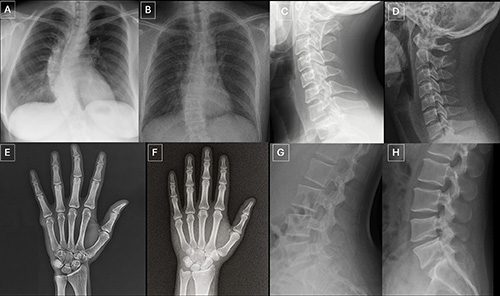

Images (JPG, TIF):

Figure 3. Anatomy-matched real and GPT-4o-generated radiographs: (A) real and (B) GPT-4o-generated posteroanterior chest radiographs, (C) real and (D) GPT-4ogenerated lateral cervical spine radiographs, (E) real and (F) GPT-4o-generated posteroanterior hand radiographs, and (G) real and (H) GPT-4o-generated lateral lumbar spine radiographs. The pairs demonstrate that GPT-4o can produce radiographically plausible images across different anatomic regions.